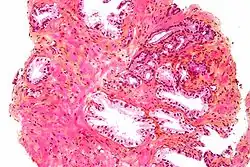

Przerzuty gruczolakoraka do płuc

Podopłucnowe przerzuty raka gruczołu krokowego szerzące się drogą naczyń limfatycznych (lymphangitic carcinomatosis)